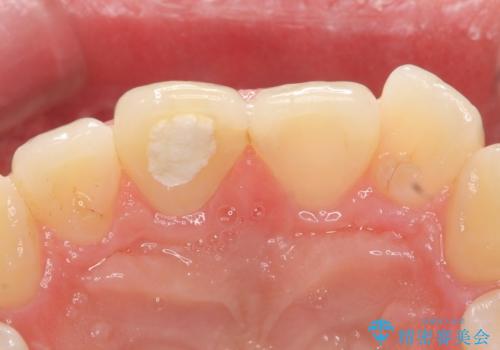

オールセラミッククラウン 痛みの引かない歯の治療

- 他院にて根管治療を行っていたが、痛みが引かないので診て欲しいといらっしゃった方の症例です。

マイクロスコープ下でラバーダムを使用しながら根管治療を行い、痛みが治まった後にオールセラミッククラウンによる補綴を行いました。